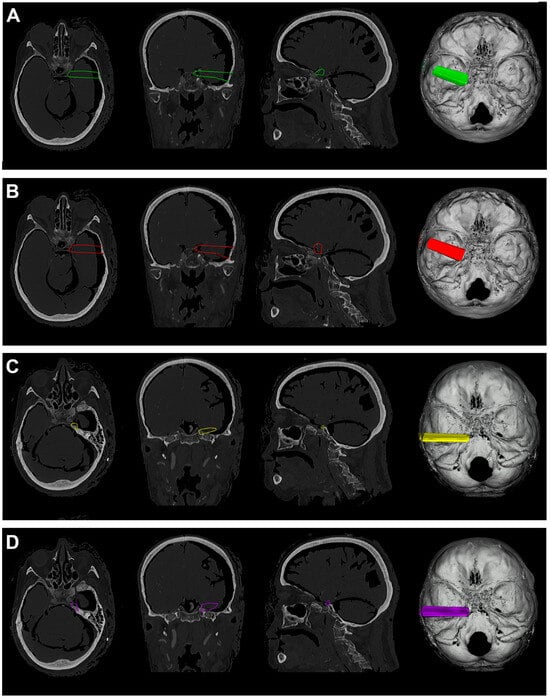

Figure 7.

(A). Exemplificative screenshot from Approach Viewer of the RSA with 10 mm of retraction. (B). Exemplificative screenshot from Approach Viewer of the RSA with 10 mm of retraction. (C). Exemplificative screenshot from Approach Viewer of the RSAS with 10 mm of retraction. (D). Exemplificative screenshot from Approach Viewer of the RSAS with 15 mm of retraction.